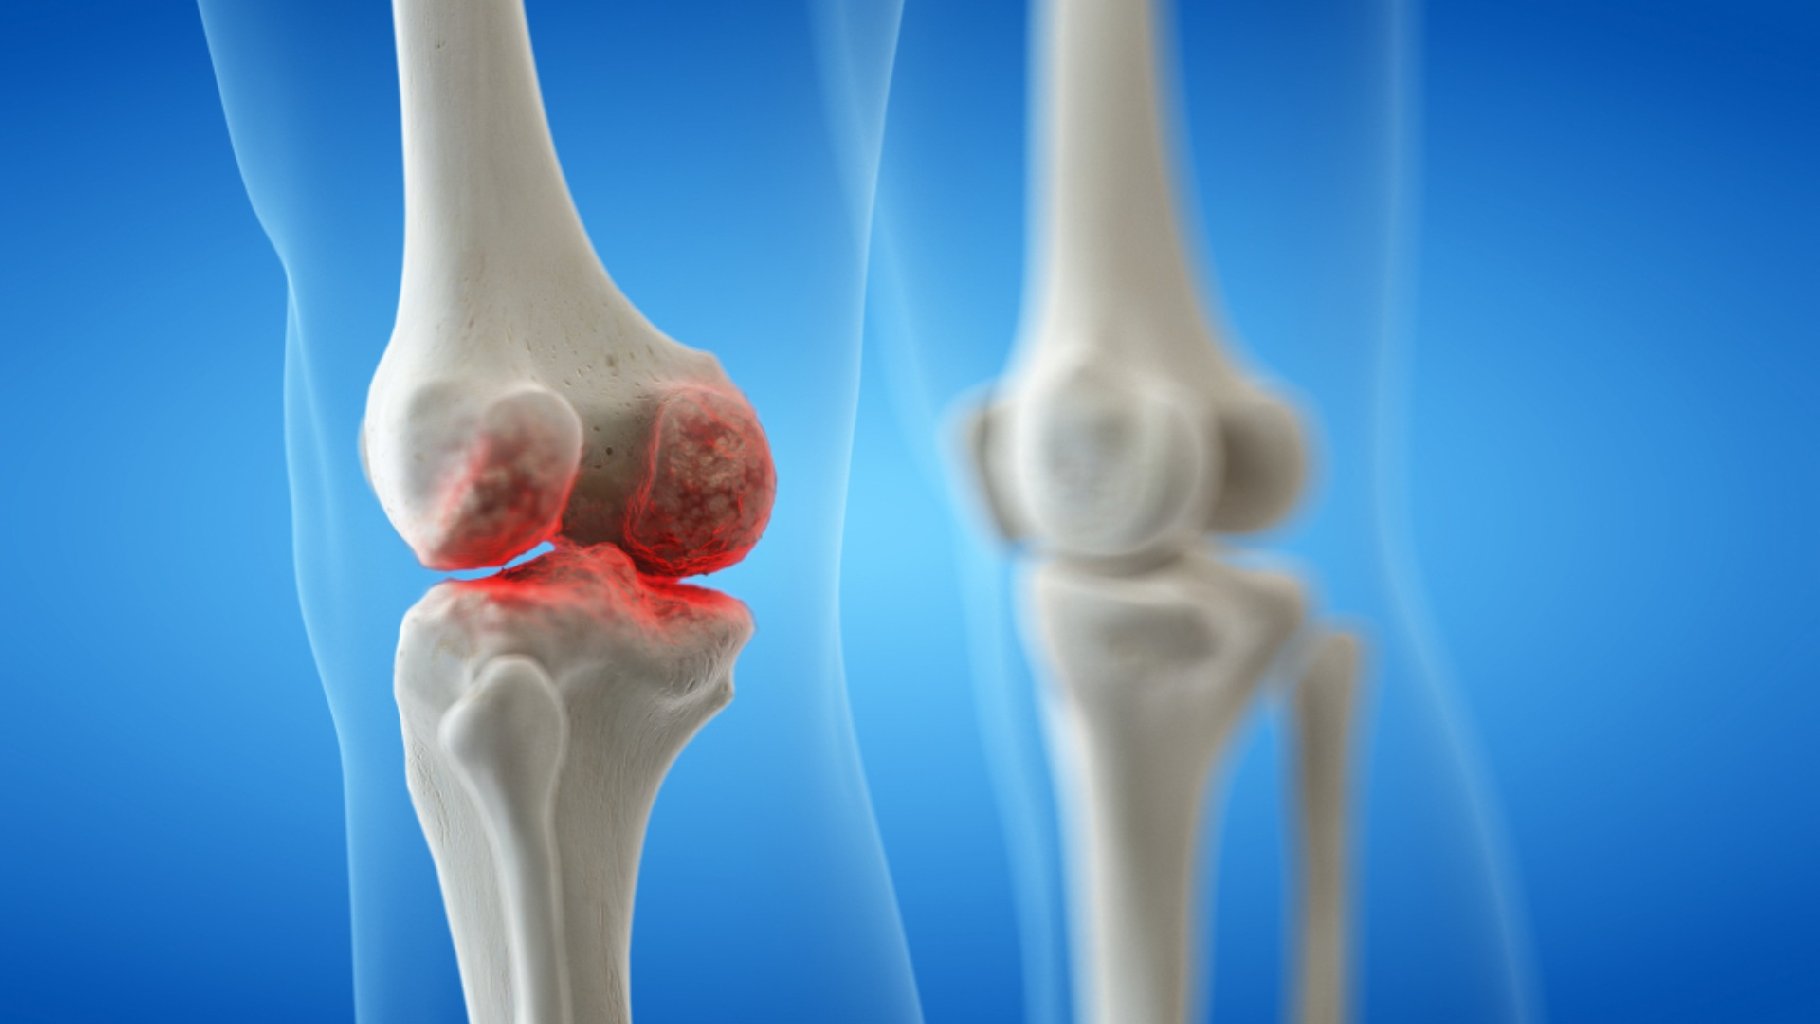

Osteoartrit (OA) Osteoartrit, ən yaygın artrit növüdür və adətən yaşla birlikdə inkişaf edir. OA, ...

Artrozun Özəllikləri: Ağrı: Oynaqlarda, xüsusilə hərəkət etdikdə və ya ağır işlər gördükdə ağrıla ...